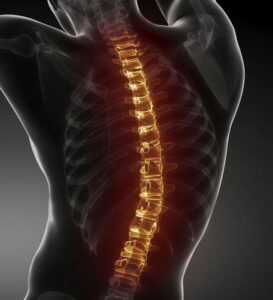

Omurga Eğriliği

Omurganın normal hizasından saparak anormal bir kıvrım oluşturmasıdır. Skolyoz, kifoz ve lordoz gibi türleri vardır. Genetik, duruş bozuklukları veya kas …

Omurga Kireçlenmesi

Omurgadaki eklemlerin zamanla aşınması ve kıkırdağın incelmesi sonucu oluşur. Hareket kısıtlılığı, sırt ve bel ağrısı yapar. Omurga kireçlenmesi sırasında kemikler …